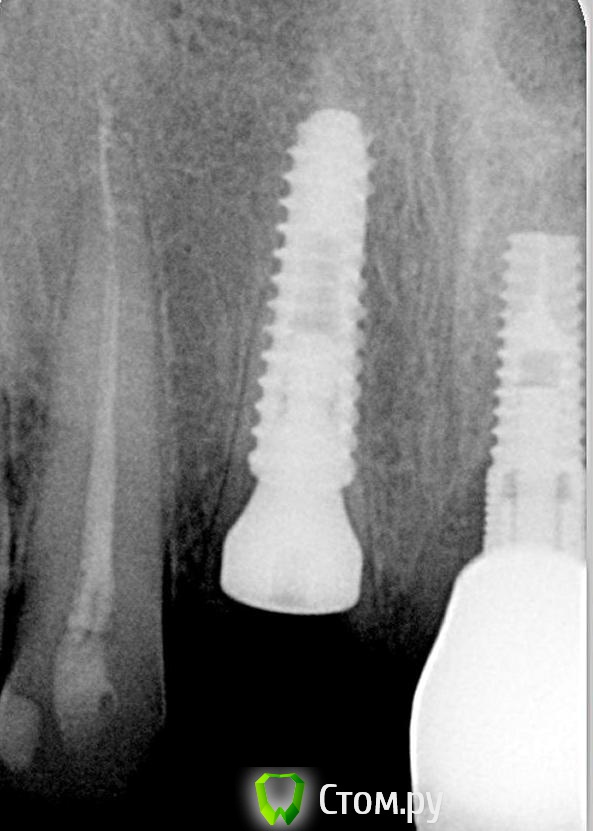

Andex Опубликовано 7 октября, 2014 Поделиться Опубликовано 7 октября, 2014 Внесу свой взгляд на тему. Мне интерестна методика - выкладываю свой кейс. Солидарен с Александром, если Вам интерестно - могу поделиться результатами и наблюдениями своих пациентов. На последнем фото - установил формирователь, тк через неделю после операции разошлись швы и сместился мною плохо мобилизованный ротированный(недостаточно) лоскут с неба - мои навыки еще далеки от идеала. Ссылка на комментарий

kriokov Опубликовано 8 октября, 2014 Поделиться Опубликовано 8 октября, 2014 Солидарен с Александром, если Вам интерестно - могу поделиться результатами и наблюдениями своих пациентов а почему в этом случае отдали предпочтение щитку?Конфигурация гребня хорошая, рядом коронка на болте в хорошем состоянии, вкрутил бы болт немедленно + графт в щель + сст, + врем коронка. ИмХо 2 1 Ссылка на комментарий

Andex Опубликовано 8 октября, 2014 Поделиться Опубликовано 8 октября, 2014 (изменено) а почему в этом случае отдали предпочтение щитку?Конфигурация гребня хорошая, рядом коронка на болте в хорошем состоянии, вкрутил бы болт немедленно + графт в щель + сст, + врем коронка. ИмХоМне понравилась теория данной методики- поэтому я пока отношусь к числу людей,кто верит в щит. Рядом винт - тоже моя работа, сделал специально 2 зуба рядом в одинаковых условиях(на одном пациенте), чтобы динамику в сравнении наглядно вести. Графт+сст+времянка - пока считаю свой уровень недостаточным для таких продвинутых методик, в основном из-за сст,тк не научился еще с ним работать как надо(( Изменено 8 октября, 2014 пользователем Andex 1 Ссылка на комментарий